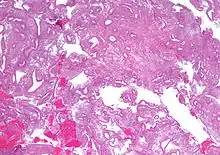

Micrograph showing simple endometrial hyperplasia, where the gland-to-stroma ratio is preserved but the glands have an irregular shape and/or are dilated. Endometrial biopsy. H&E stain. | |

Endometrial hyperplasia is a condition of excessive proliferation of the cells of the endometrium, or inner lining of the uterus.

Like other hyperplastic disorders, endometrial hyperplasia initially represents a physiological response of endometrial tissue to the growth-promoting actions of estrogen. However, the gland-forming cells of a hyperplastic endometrium may also undergo changes over time which predispose them to cancerous transformation. Several histopathology subtypes of endometrial hyperplasia are recognisable to the pathologist, with different therapeutic and prognostic implications.[3]